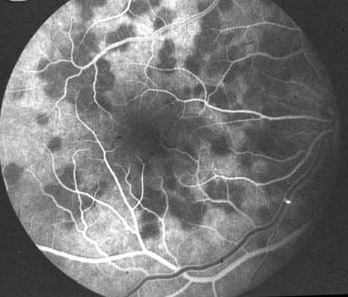

交感性眼炎(#1,2 血管造影片)

交感性眼炎(#1,1)